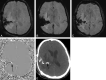

Background and purpose: SWI is a unique pulse sequence sensitive to both hemorrhage and calcification. Our aim was to retrospectively assess the ability of SWI to detect intratumoral calcification in ODs compared with conventional MR imaging.

Materials and methods: Using CT as criterion standard, the MR imaging findings from 71 patients (33 males, 38 females; mean age, 42.5 years) with pathologically proved OD were retrospectively evaluated. We classified the MR imaging data into SWI data (MRSWI) and traditional pulse sequences (MRnoSWI). The sensitivity and specificity of the MRnoSWI (n = 71) were compared with that of the MRSWI (n = 13) independently and also for matched-paired data (n = 13). The Fisher exact test was applied to the matched-pair data for statistical evaluation.

Results: For paired data of MRSWI and MRnoSWI (n = 13), there was significantly increased sensitivity of MRSWI (86%) for the detection of intratumoral calcification in OD compared with the MRnoSWI (14.3%) (P = .015, Fisher exact test) by using CT as the criterion standard. The overall accuracy of MRSWI for the paired data was also significantly greater (P = .048). The specificities were not significantly different (P = .773). The sensitivity of MRSWI (n = 13) was 86%, and for MRnoSWI (n = 71), it was 33.3%. Specificity of MRSWI was 83%, and for MRnoSWI, it was 95%.

Conclusions: SWI is better able to detect calcification in ODs than conventional MR imaging pulse sequences.